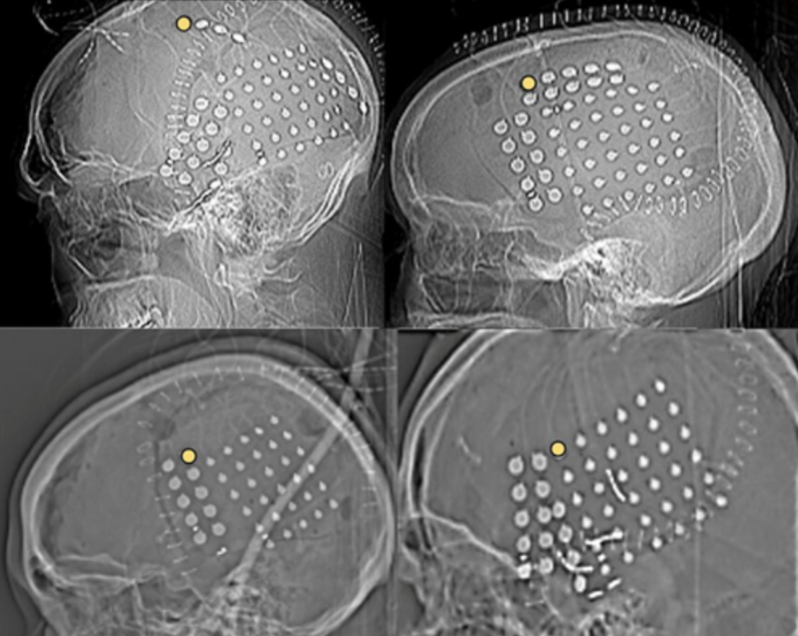

Invasive Techniques

involve placing electrodes directly on the brain or within it to record neuronal activity.

They are used in research and clinical settings, particularly in epilepsy treatment.